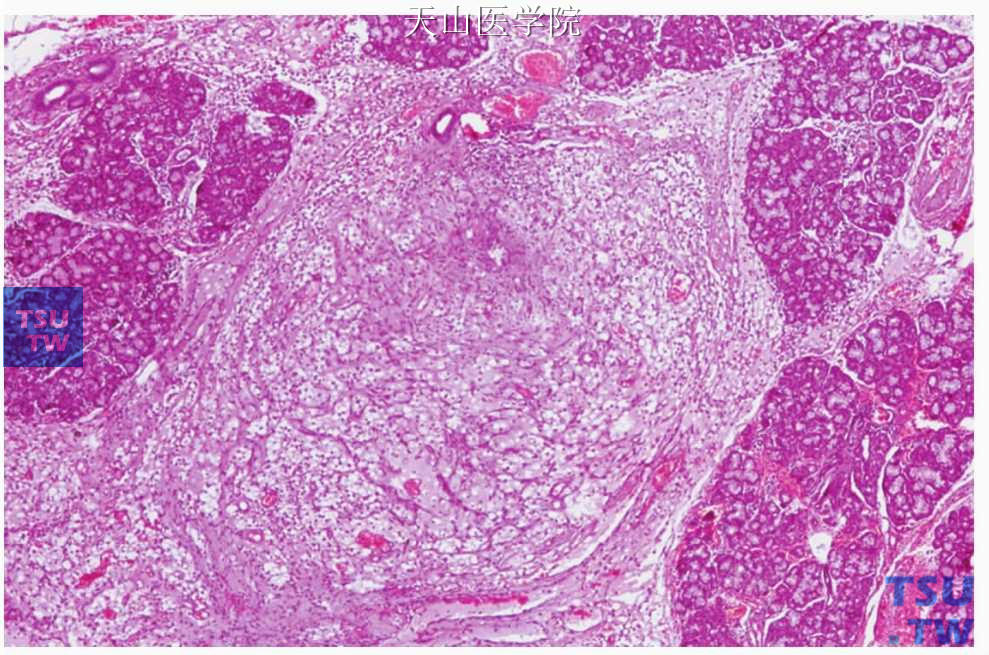

舌下囊肿(唾液腺瘤样病变的临床病理)

舌下囊肿(ranula)是发生在舌下腺的黏液囊肿。Ranula一词来自于拉丁单词“rana”(意为青蛙)。早在1676年Wiseman在他的外科学教科书中就提到舌下囊肿来自于舌下腺并且